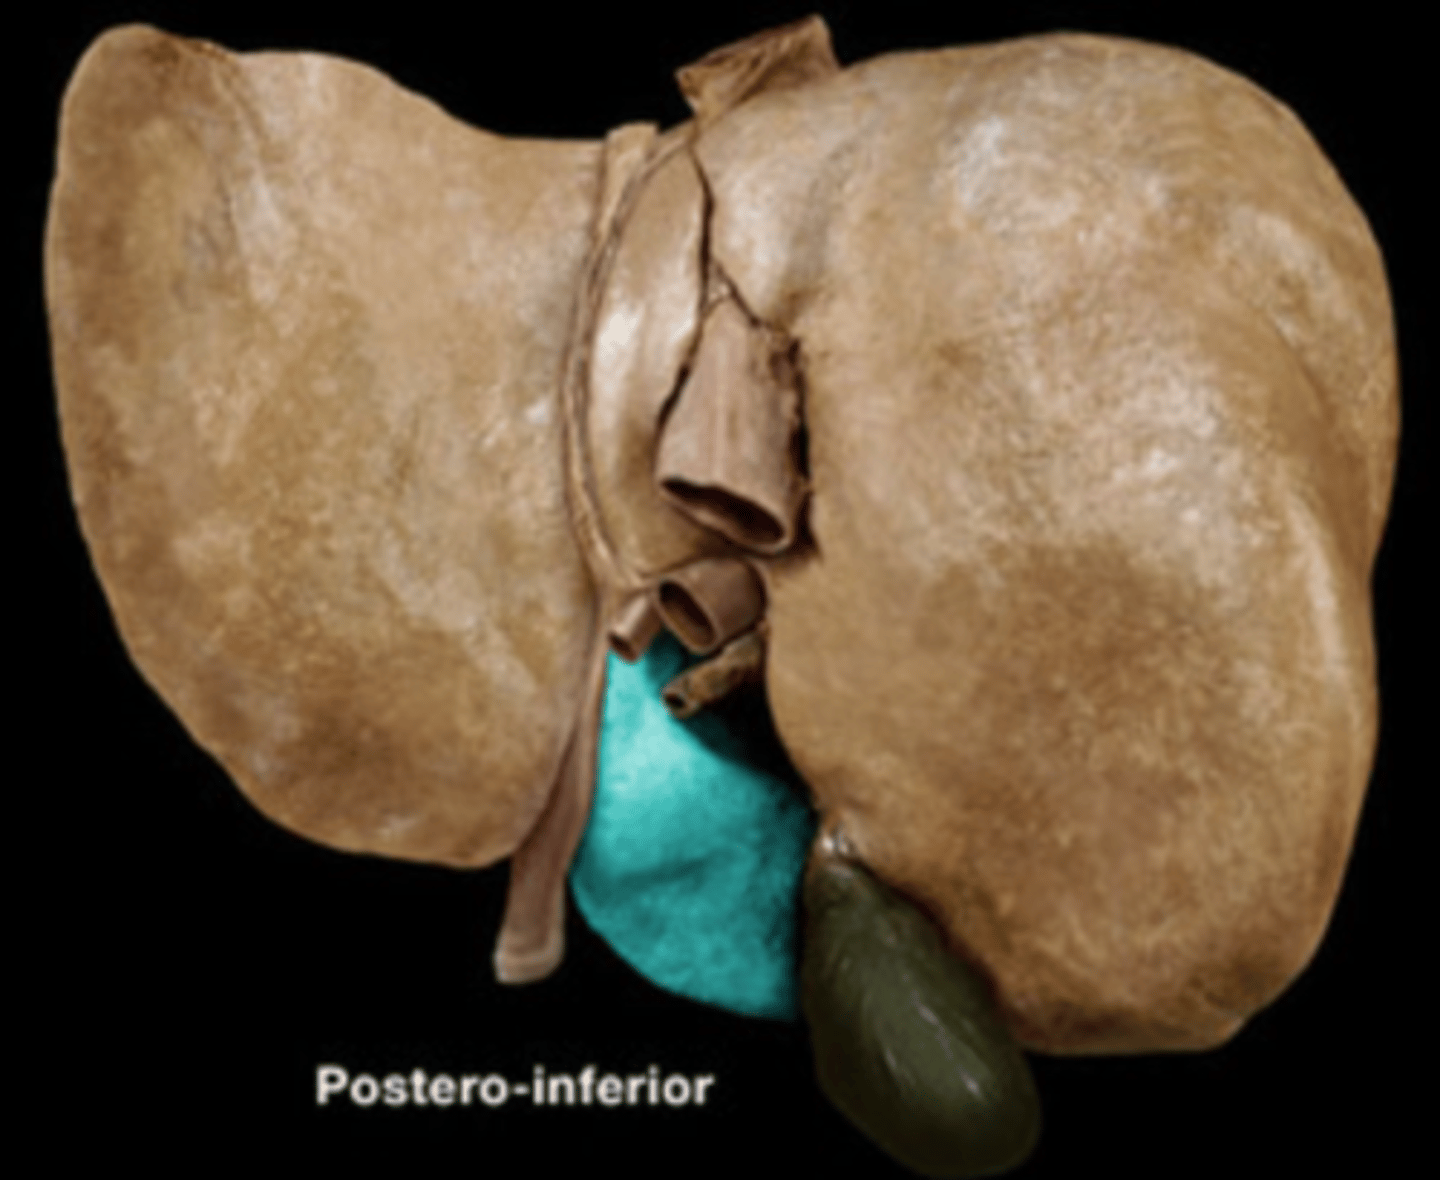

Caudate Lobe of Liver

Quadrate Lobe of Liver

Falciform Ligament

Ligamentum Teres

Gall Bladder